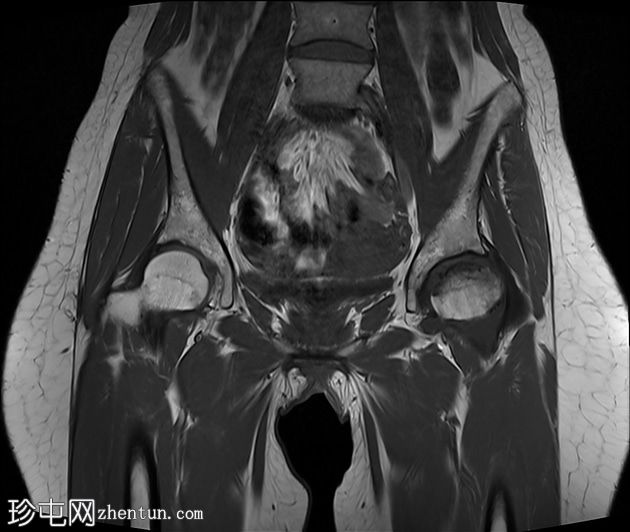

2.jpg

冠状位

T1加权像

左侧股骨头:

T1和T2加权像上可见股骨头前上缘呈蛇形低信号,勾勒出一个地理区域,STIR序列上可见邻近骨髓水肿。

软骨下骨折/新月征,关节面局灶性凹陷——符合软骨下塌陷。

关节间隙中央保持完整,但股骨头轮廓异常,系塌陷所致。

右侧股骨头:

未见骨髓信号异常或软骨下骨折。股骨头轮廓保持完整

关节周围结构:无大量关节积液,无骨关节炎性关节间隙狭窄或边缘骨赘,提示无晚期继发性退行性改变